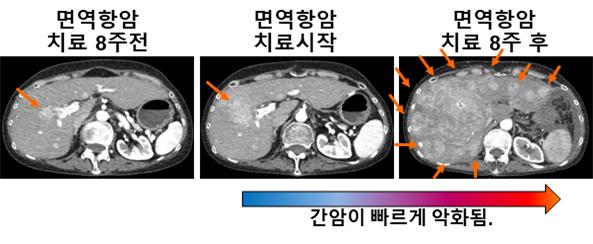

연구팀은 국내 간암 환자를 분석한 결과 면역항암제 치료를 받은 189명의 환자 중 10명 중 1명의 비율로 급성진행현상이 나타날 수 있음을 알아냈다.

아울러 면역항암제 피료 전후 암성장율과 암성장키네틱이 모두 4배 이상 증가했으며 호중구·림프구비율(NLR)이 높을수록 치료반응률이 급격히 감소하고 급성진행 확률이 급증했다.